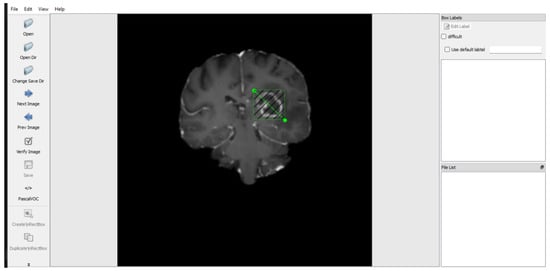

3.2. Data Preparation

3.3. Data Preprocessing